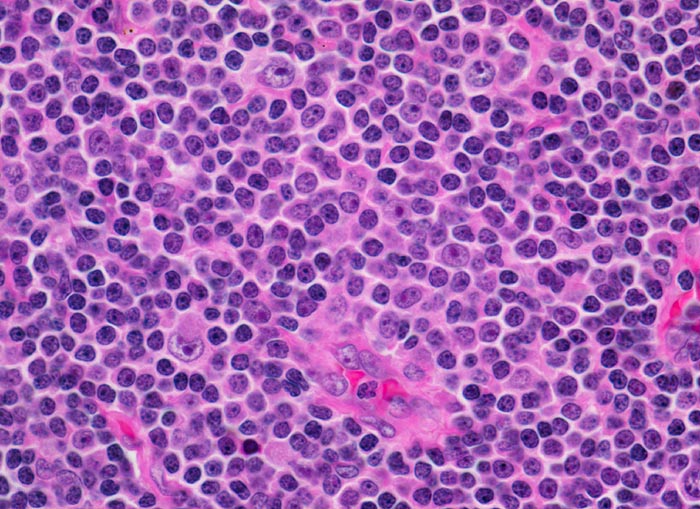

Befallene Lymphknoten weisen eine Zerstörung der normalen Architektur auf. Die neoplastischen Zellen bilden auf einem dunklen Hintergrund kleiner Zellen heller erscheinende Pseudofollikel bestehend aus vermehrt Paraimmunoblasten. Der dominierende Zelltyp ist etwas grösser als ein normaler Lymphozyt, der Kern ist rund und das Chromatin verklumpt. Der Zytoplasmasaum ist sehr schmal.

• Vergrösserter Lymphknoten mit zerstörter Lymphknotenarchitektur.

• Diffuse Infiltration des Lymphknotens durch monomorphe kleinlymphozytische Lymphomzellen.

• Unscharf begrenzte helle Areale (Proliferationszentren) auf dunkelblauem Hintergrund.

• Proliferationszentren (=Pseudofollikel) bestehend aus Lymphozyten und Paraimmunoblasten.